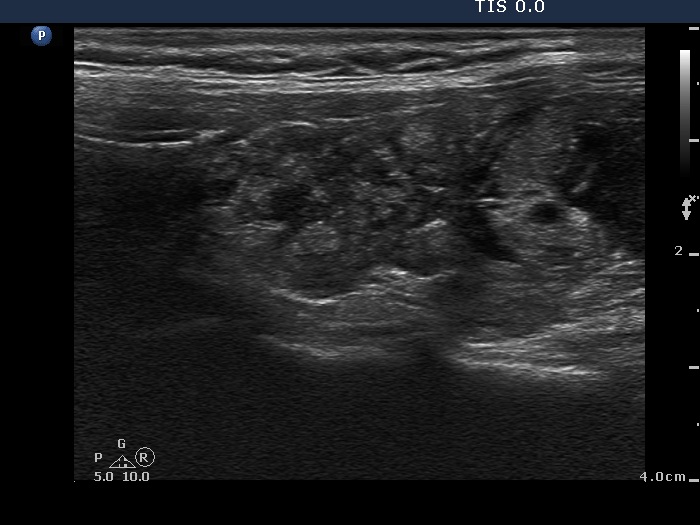

Ethanol sclerotherapy: thyroid cysts - Case 7

First session of therapy (ultrasonographic picture 4)

Right lobe, horizontal view